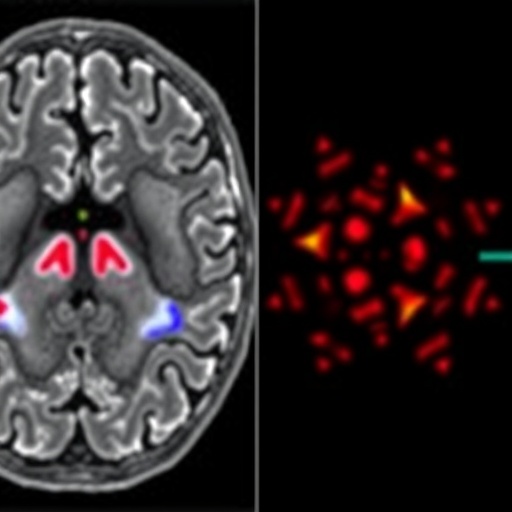

The innovative technology promises to alleviate the escalating pressures faced by healthcare systems worldwide, particularly the increasing demand for MRI scans which strains radiology departments and neurologists. Unlike traditional approaches that depend heavily on manual analysis of MRI data, Prima utilizes a vision language model (VLM) architecture, enabling it to simultaneously process multimodal inputs including images, videos, and textual clinical data. This approach mirrors the comprehensive assessment methods used by expert radiologists.

Prima was trained on an unprecedentedly vast dataset comprising over 200,000 MRI studies encompassing 5.6 million imaging sequences, spanning decades of digitized radiology records from the University of Michigan Health system. This expansive training corpus, incorporating both imaging data and patients’ clinical histories alongside physicians’ indications for ordering scans, has allowed the system to develop a broad and nuanced understanding of neurological health, enhancing its diagnostic capabilities across more than 50 distinct radiologic diagnoses.

Prima’s architecture as a vision language model is especially notable for its integration of multi-format data inputs. Unlike prior AI models limited to narrow tasks—such as lesion detection or dementia risk prediction—Prima embodies a holistic analytic paradigm. It assimilates imaging information in concert with patient history to construct a comprehensive clinical context, thus reflecting the multifaceted diagnostic process employed by human radiologists.